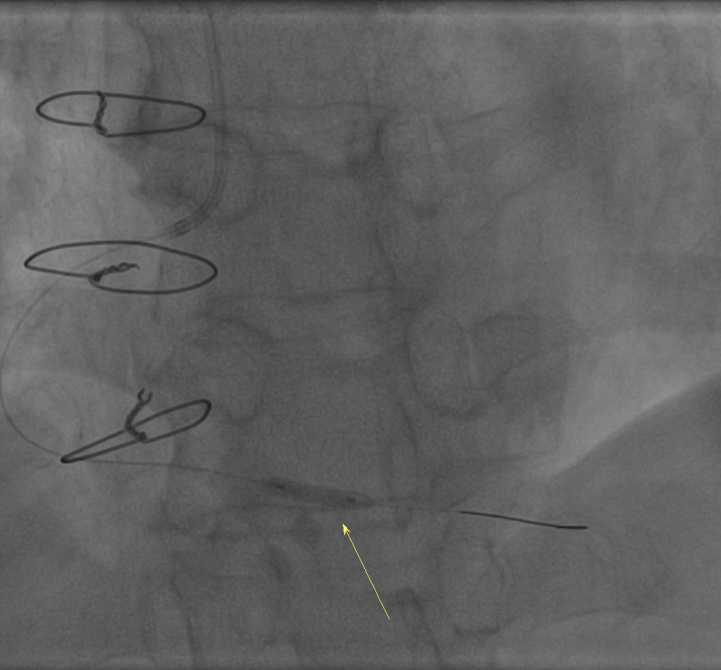

图4、5 球囊扩张和术后支架

经过了近1个小时的手术后,医生们成功为患者植入一枚支架,术程顺利。术后,患者胸痛症状消失。(供稿:韦冬英 审核:蒋源蔓)